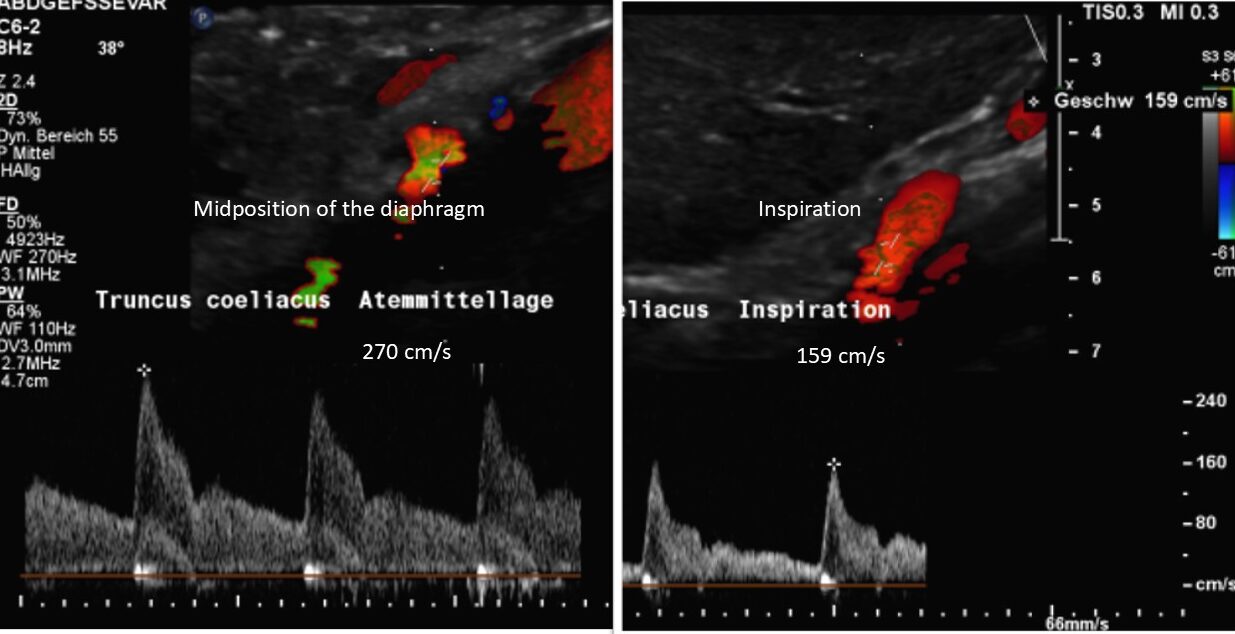

The chronic regional pain syndrome component was fuelled by activation of the sympathetic nervous system, resulting from compression of the largest sympathetic nerve plexus: the celiac plexus. In this patient, the coeliac plexus was severely compressed by a tightly straddling median arcuate ligament at the origin of the coeliac trunk. This is another consequence of increased lumbar lordosis, which pulls the arch formed by the two diaphragmatic crus legs tight.

In arcuate ligament syndrome, the coeliac plexus is compressed between the lower margin of the aortic hiatus and the coeliac artery. This results in persistent mechanical activation of this large sympathetic nervous network.